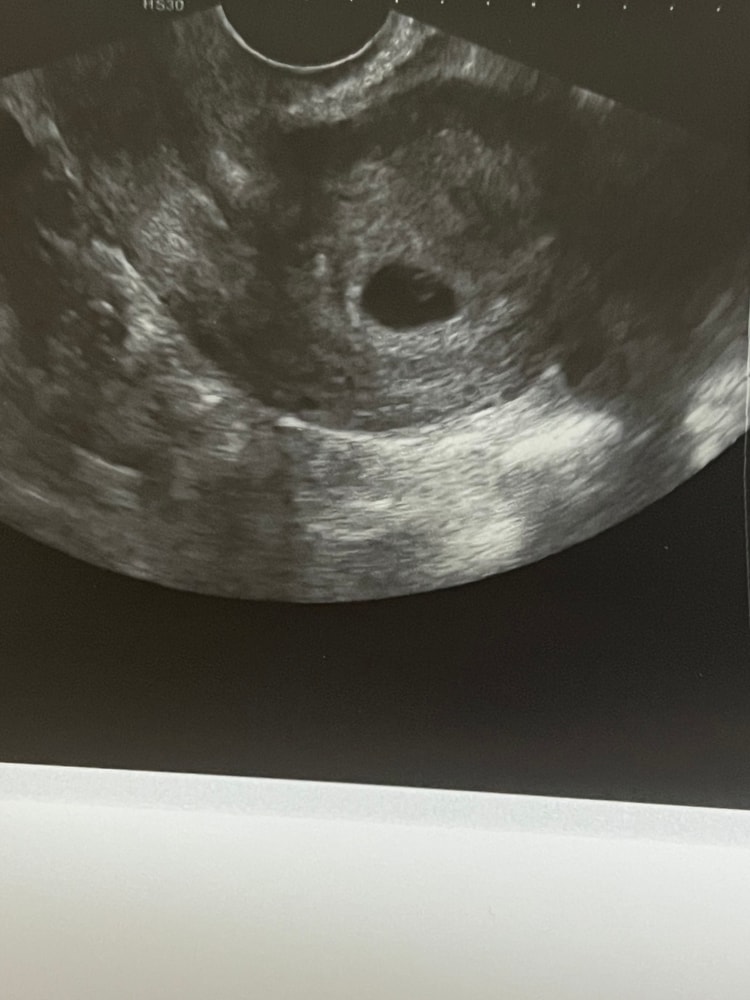

Узи 5-6 недель, посмотрите пожалуйста

Обследования, узи, анализыМне кажется, или под желточным мешочком как раз что-то похожее на эмбриона ?🤔

У меня похожая ситуация, срок на момент узи был 5+3, пя 9, жм 4. Я пошла в первую попавшуюся клинику, потому что были незначительные бежевые выделения. Меня посмотрели и сказали: ну знаете тут нет эмбриона, я и так и так кручу ничего нет, возможно у вас уже и беременность отторгается, а может и гематома кровит. Хотя тоже было на узи колечко- жм без «бриллианта»- эмбриона. Неадекватная попалась какая-то, пойду 15 числа смотреть что там да как. Но уверена, покажутся эмбриончики чуть попозже наши)

А какой размер пя поставили и жм? Так сложно сказать еще, через недельку бы вам повторить узи